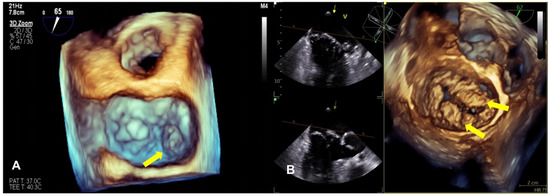

Compared with 2D echocardiography, 3D echocardiography facilitates the differentiation between leaflet prolapse and billowing (Figure 2). It provides a more accurate understanding of the mitral valve’s structure and function, the specific location of the prolapse, and whether the commissure is involved, and can accurately define and measure the volume of the ventricle and the understanding of mitral annulus dynamics and whether MR pathophysiology has improved, especially using real-time 3D transesophageal echocardiography (TEE) [7,74,75]. The advent of 3D technology has also led to significant improvements in the accuracy of the MR severity assessment. Finally, 3D TEE is considered critical for the pre- and intra-procedural evaluation of mitral valve anatomy and MR mechanisms and is widely used [76].

Figure 2.

The panels show a 3D TEE surgical view of mitral valve prolapse. (A) This image shows the dislocation of the posterior mitral leaflet (P3) during systole (yellow arrow). (B) This image is typical of Barlow syndrome, which presents as bileaflet prolapse (yellow arrow).